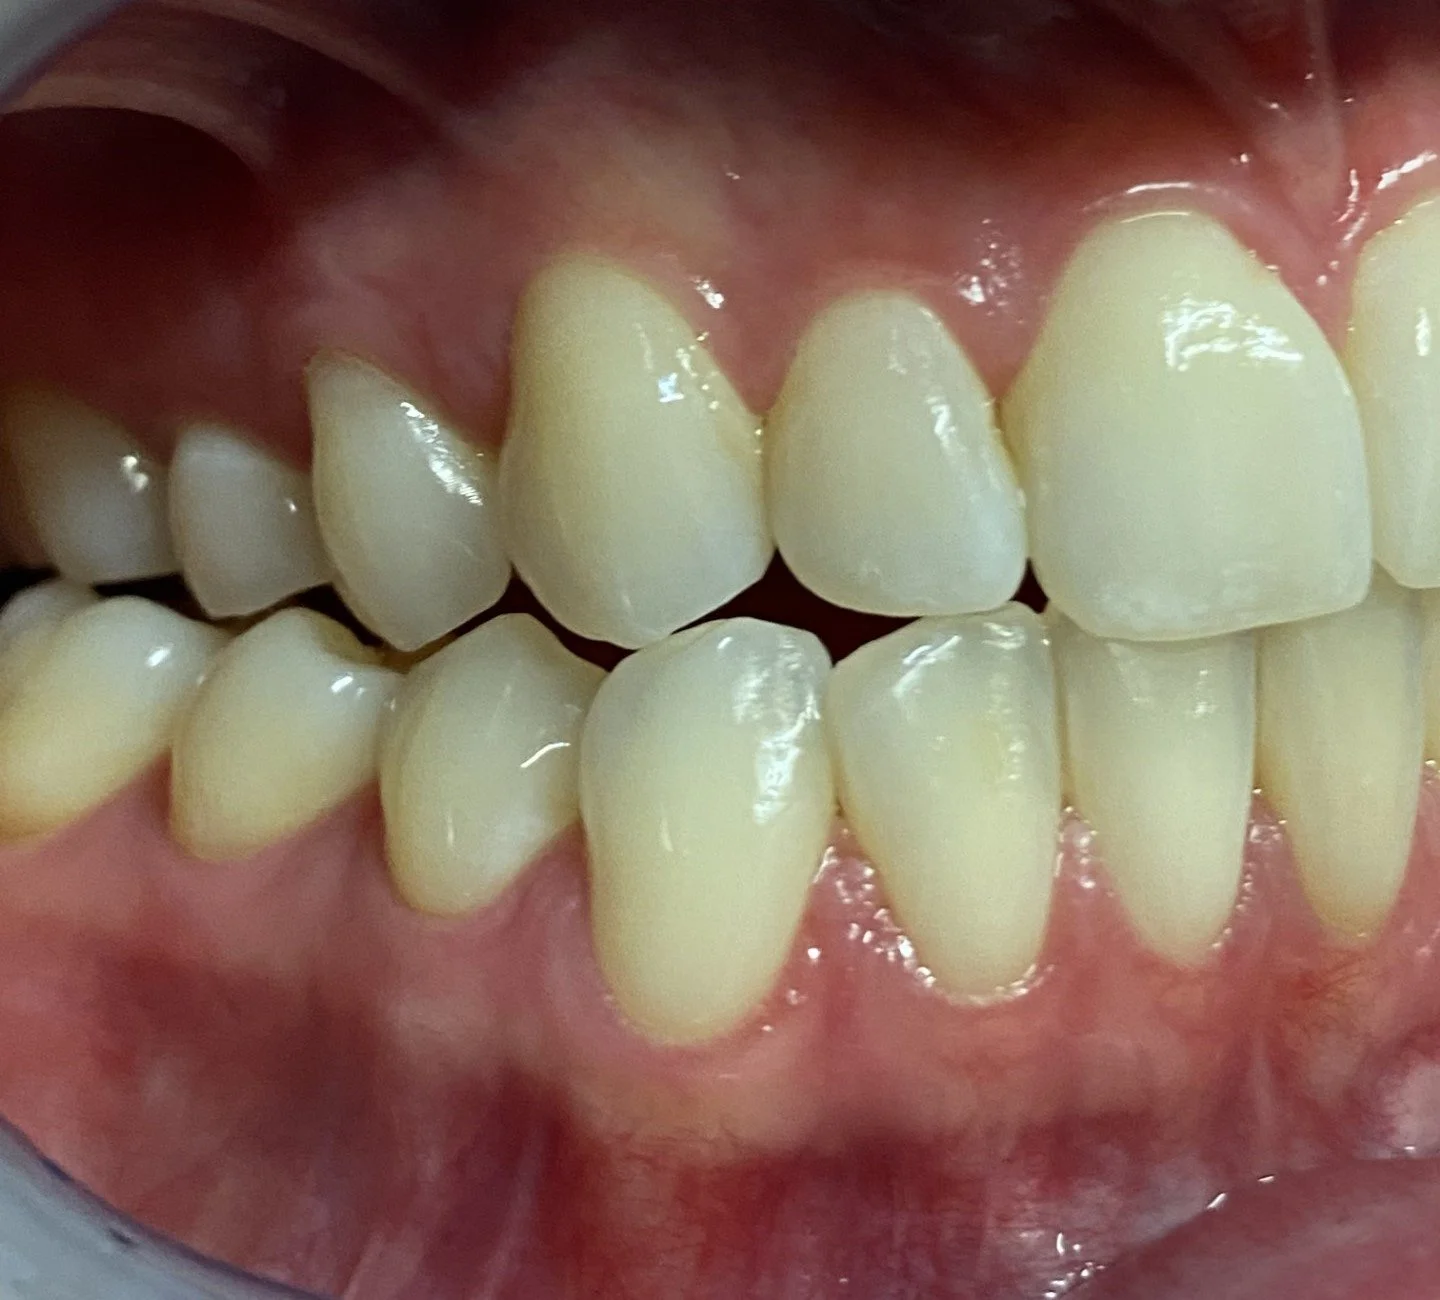

Now the bio-designed lower right 43 temporary crown creating a right protective bite.

We can clearly see that the lower jaw has moved into an extreme right jaw movement but has been stabilised and restricted by the engagement of the bio-designed lower final canine crown and upper resin overlay.

The completed aesthetic and functional occlusal bite case in hinge bite.